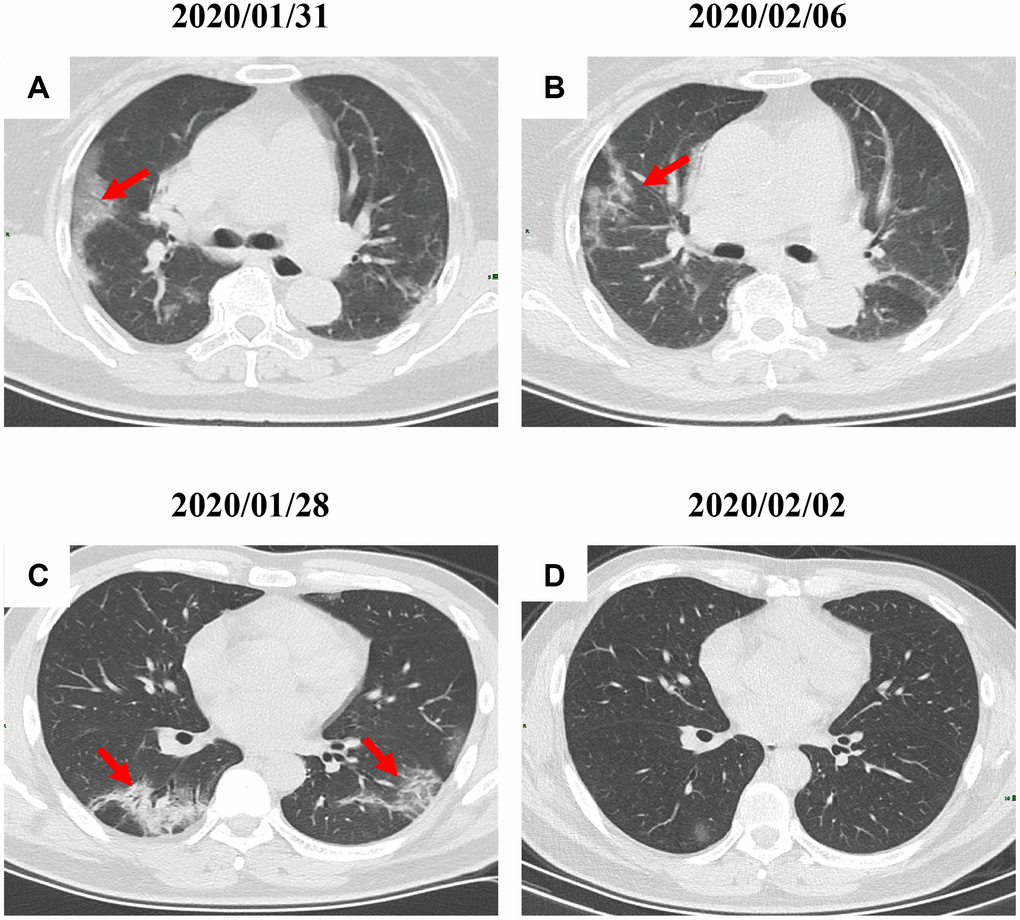

By Mar 23, 2020, 60 (60/66, 91%) patients had been discharged. 6 (6/66, 9%) patients were still in hospital, and two patients had died because of ARDS. Patient 1, 78-year-old man with hypertension, who died on day 15 after admission (Figure 1B). Patient 2, 47-year-old man with type 2 diabetes, whose CT scan presented rapid radiology progression (Figure 3A, 3B). The radiological change of COVID-19 pneumonia develops fast during the first seven days (Figure 3C, 3D). Some of patch lesion could be absorbed and change into reticular spline lesion (Figure 4A, 4B). Meanwhile, some patients achieved rapid recovery with significant improvement of CT sign (Figure 4C, 4D) and clinical symptoms. We also did some CT follow-up scans for few patients, which showed the aggravated progression of disease since admission and rapid recovery after treatment (Figures 5 and 6). Disappearance of lesions and significant improvement of clinical symptoms were observed in two patients (Figure 5: a 54-year-old male patient; Figure 6: a 54-year-old female patient).

Figure 4. Radiological improvement of two COVID-19 pneumonia patients. (A, B) Patch lesions were absorbed and changed into reticular spline ones (a 31-year-old female patient); (C–D) Significant improvement of CT sign was achieved in a 22-year-old male patient. Typical lesions were marked with red arrows.

Figure 5. A serial CT images after admission of a 54-year-old male patient. (A) Patch ground-glass opacity was observed in the middle right lobe. (B) 5 days later, significant larger patch ground-glass opacities were observed in bilateral lungs. (C) Follow-up CT scans on day 13 after admission show a remarkable improvement. Typical lesions were marked with red arrows.

Figure 6. A serial CT images after admission of a 54-year-old female patient. (A) Patch ground-glass opacity mainly located in the left lower lobe. (B) Significant larger patch ground-glass opacities were observed in both lower lobes after 8 days. (C) Follow-up CT scans on day 20 after admission show a remarkable improvement. Typical lesions were marked with red arrows.